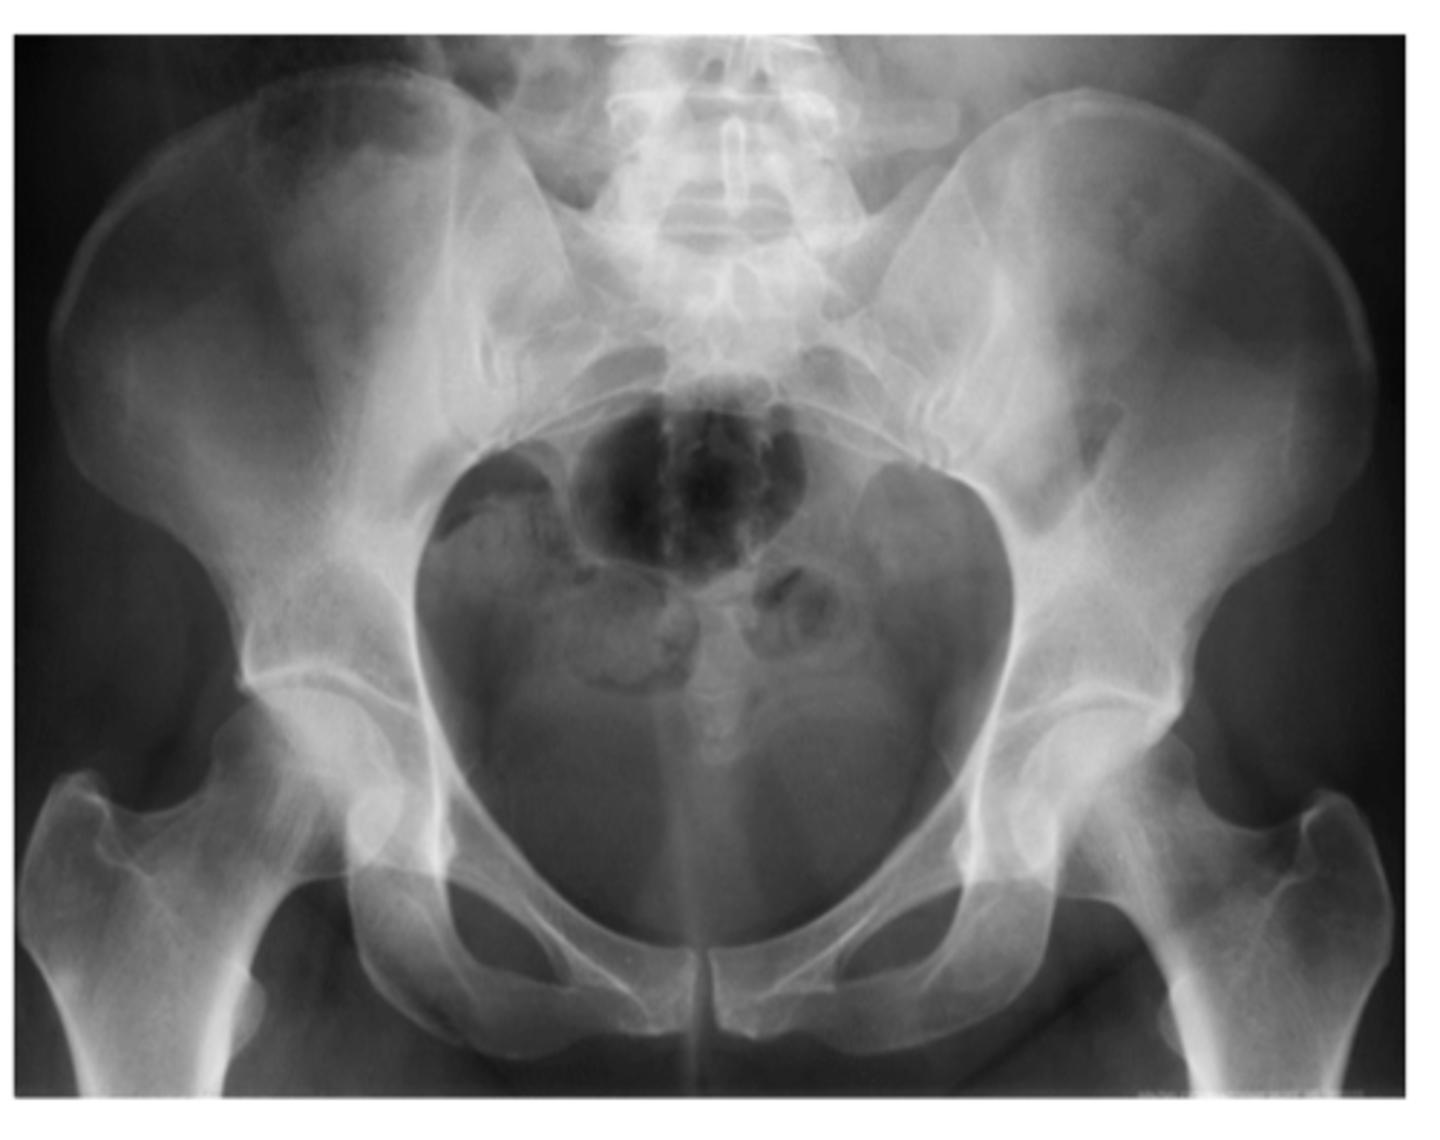

List the sub-components of (A) alignment: general architecture

- Aberrant size of bones

- Supernumerary bones (i.e., extra bones)

- Congenital abnormality

- Absence of any bones

- Developmental deformities

List the sub-components of (A) alignment: general contour

- Irregularities

- Cortical outline

- Spurs and osteophytes

- Fracture

List the sub-components of (A) alignment: alignment related to adjacent bones

- Dislocation

- Subluxation

List the 3x components of (B) bone density when interpreting a plain film radiograph

1. General bone density

2. Textural abnormalities - trabeculae

3. Local density changes - sclerosis

What is sclerosis?

Hardening of the bone tissue at the joint line (often a primary indicator of OA)

List the 3x components of (C) cartilage space when interpreting plain film radiographs

1. "space" can be an indirect assessment of radiolucent cartilage

2. Subchondral bone -- sclerosis vs. erosions

3. Epiphyseal plates

If we identify a loss of joint space on a plain film radiograph, what may this imply?

Loss of cartilage (primary indication of OA, along with bone spurs and sclerosis)

What are erosions? What do they indicate?

Scalloped, notched edges that indicate cartilage damage and wearing away of bone -- think rheumatic diseases (RA, PA, etc.)